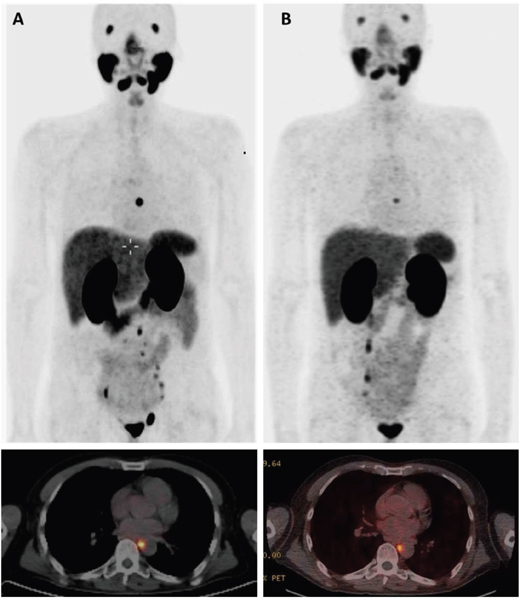

In 2016, the patient had a third episode of continuously rising PSA. A restaging 68Ga-PSMA HBED-CC PET/CT in July 2016 showed new pathologic uptakes in a mediastinal lymph node and several infradiaphragmal lymph nodes (Figure 2A). At that time, he had an ECOG performance status of 0, he had no pain, and had normal levels of thrombocytes. PSA was 0.6 ng/ml. However, the patient preferred to be treated with 177Lu-PSMA-617 RLT. He wanted to postpone chemotherapy with docetaxel. In July and September 2016, he was given two cycles of 177Lu-PSMA-617 RLT with a radioactivity of 6 gigabequerel (GBq) in both cycles [6]. The interval between the two cycles was eight weeks. Dosimetric analyses indicated a cumulative tumor dose of 37.7 Gy. The dose corresponded to a dose (EQD2) of 226 Gy. We calculated the EQD2 for external beam radiotherapy given with a standard fractionation of 2 Gy per fraction and with alfa/beta ratio for PC estimated as 1.5. The first cycle of 177Lu-PSMA-617 RLT caused acute nausea. But with use of anti-emetic drugs, the patient avoided nausea in connection with the second cycle. Otherwise the 177Lu-PSMA-617 RLT did not cause acute adverse effects.

Figure 2: 68Ga-PSMA-HBED-CC PET/CT before and after treatment with 177Lu-PSMA-617 RLT. Panel A shows PET/CT before treatment July 2016 with the strongest lymph node uptake in a paraesophageal lymph node and uptakes in lymph nodes in the obturatory regions and sites in left internal and common iliac nodes. Panel B shows PET/CT after treatment November 2016 with uptake only in the mediastinal lymph node.

Follow-up 68Ga-PSMA HBED-CC PET/CT was carried out in November 2016 and February 2017 (Figure 2B). In the follow-up, the mediastinal lymph node showed a reduction of SUVmax from 21.6 to 8.6. All other pathologic sites had normalized. Total tumor volume had decreased from 18 cm3 to 1.5 cm3. From December 2016 to May 2017 PSA has been unmeasurable. In December 2016, the combination of abiraterone-and prednisone was switched to a combination of abiraterone 150 mg per day and dexamethasone 1 mg per day. In May and June 2017, he had a slight rise of PSA. Until June 2017, the patient had no chronic adverse effects.